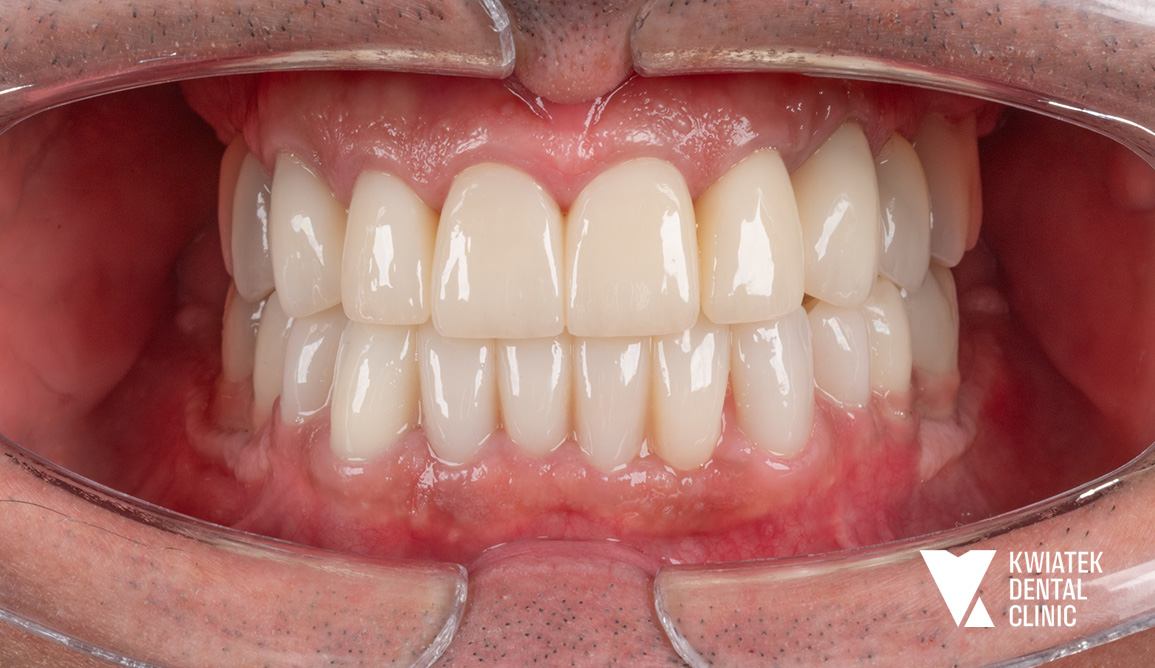

Pełna rekonstrukcja zwarcia i estetyki - historia wymagającej metamorfozy

Pacjent zgłosił się do kliniki z zaawansowanymi problemami stomatologicznymi: licznymi ubytkami próchnicowymi, brakami zębowymi, starciem zębów oraz zaburzeniami zwarcia. Leczenie obejmowało kompleksową diagnostykę, leczenie zachowawcze i endodontyczne, zabiegi chirurgiczne, implantację oraz wieloetapową odbudowę protetyczną. Efektem terapii jest perfekcyjnie zbalansowany zgryz, najwyższy komfort funkcjonowania oraz naturalnie piękny uśmiech, który podkreśla indywidualny charakter pacjenta i pozwala mu w pełni cieszyć się nim każdego dnia.